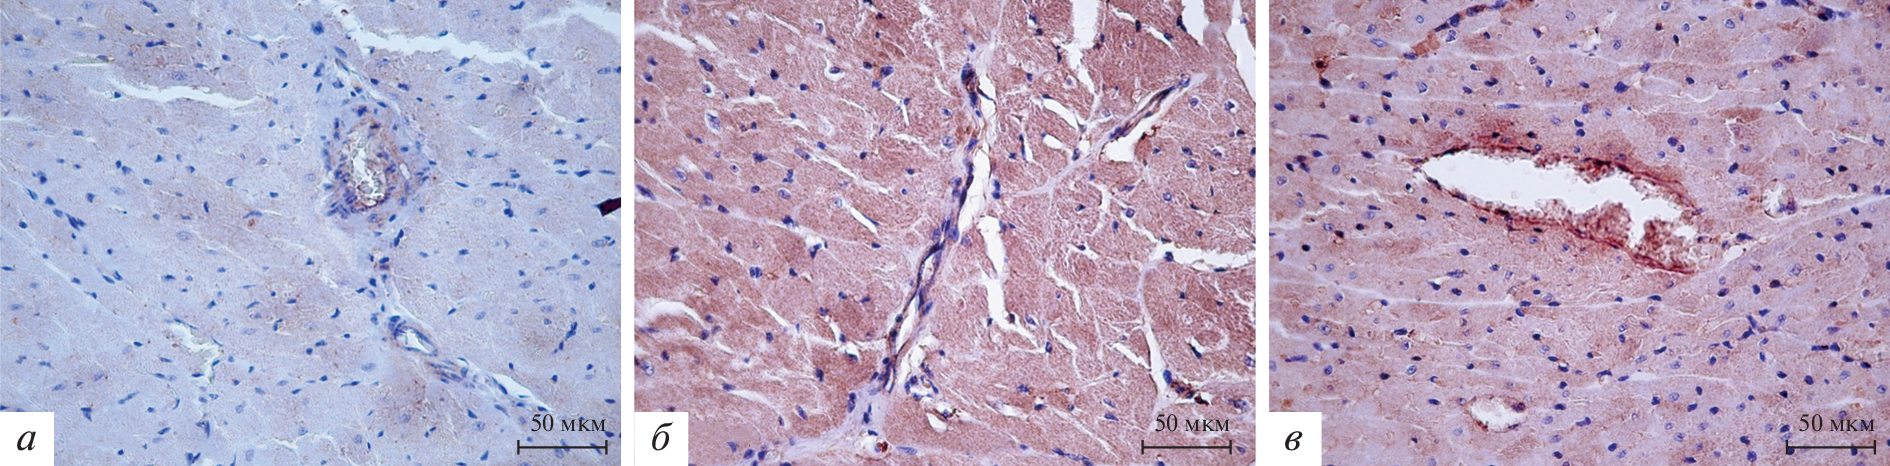

Проведено иммуногистохимическое выявление матриксных металлопротеиназ (MMP) 2 и 9 в миокарде левого желудочка сердца преждевременно рожденных (21 и 21.5 сут беременности) и доношенных (22 сут беременности) крыс на 42, 56 и 180 сут постнатального периода онтогенеза. Интенсивность иммунопозитивного окрашивания оценивали полуколичественно. Преждевременное рождение приводит к повышению интенсивности иммунопозитивной реакции на MMP-2 и MMP-9 в стенке левого желудочка сердца крыс. Повышение интенсивности позитивной реакции на MMP-2 в левом желудочке сердца крыс наблюдается тем раньше, чем больше степень недоношенности. Интенсивность позитивной реакции на MMP-9 в левом желудочке сердца самцов крыс растет с увеличением степени недоношенности. Повышение интенсивности позитивной реакции на MMP-2 и MMP-9 в стенке левого желудочка самок крыс вследствие преждевременного рождения определяется исключительно у животных, рожденных на 21-е сут беременности, то есть при большей степени недоношенности.